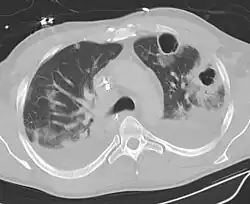

| Computed tomography (CT) scan of chest showing bilateral pneumonia with abscesses, effusions, and caverns. 37-year-old male. | |

Lung abscess is a type of liquefactive necrosis of the lung tissue and formation of cavities (more than 2 cm)[1] containing necrotic debris or fluid caused by microbial infection.

Lung abscesses are often on one side and single involving posterior segments of the upper lobes and the apical segments of the lower lobes as these areas are gravity dependent when lying down. Presence of air-fluid levels implies rupture into the bronchial tree or rarely growth of gas forming organism.